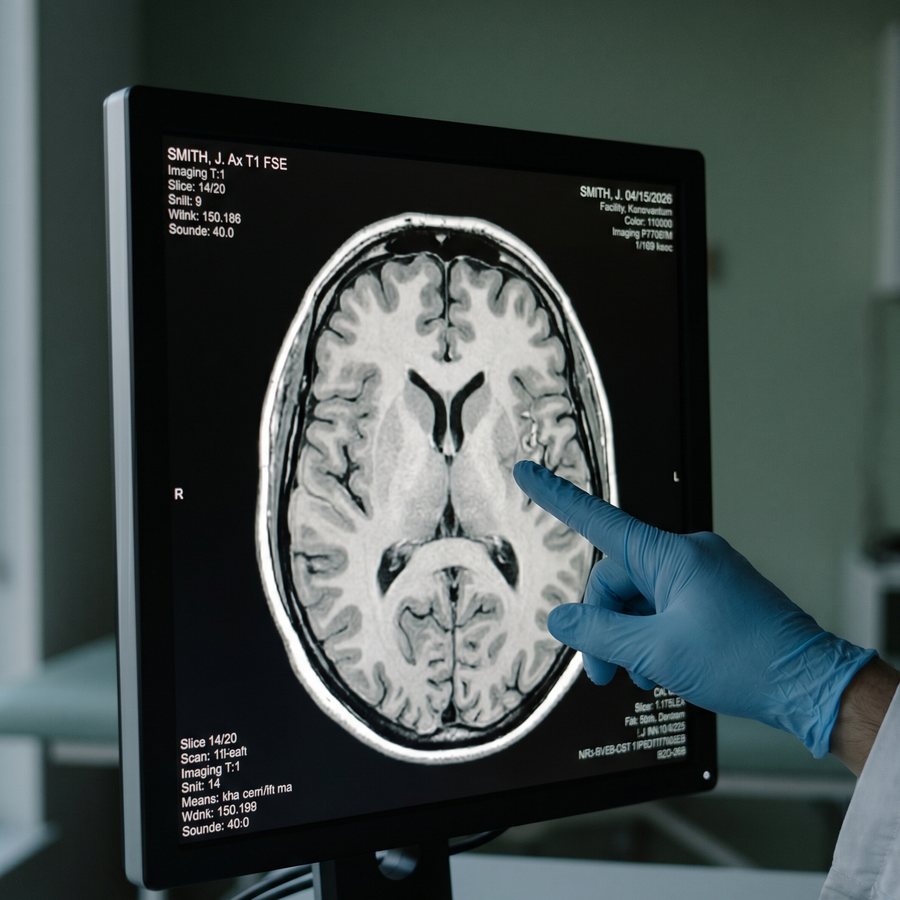

A radiologist's gloved hand pointing at an axial brain MRI on a high-resolution monitor — illustrative, no identifiable face.

Dr. Rajesh Balachandran

Consultant Radiologist

• MD (Manipal), DNB (Radio-diagnosis)

• Fellowship: MR Neuroradiology (Toronto)

• Areas of clinical practice: neuroimaging, brain volumetrics

• MMC Reg. No. pending registration